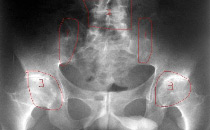

骶髂关节

例子

病症描述:AS较早的变化发生在骶髂关节。该处的X线片显示软骨下骨缘模糊,骨质糜烂,关节间隙模糊,骨密度增高及关节融合。